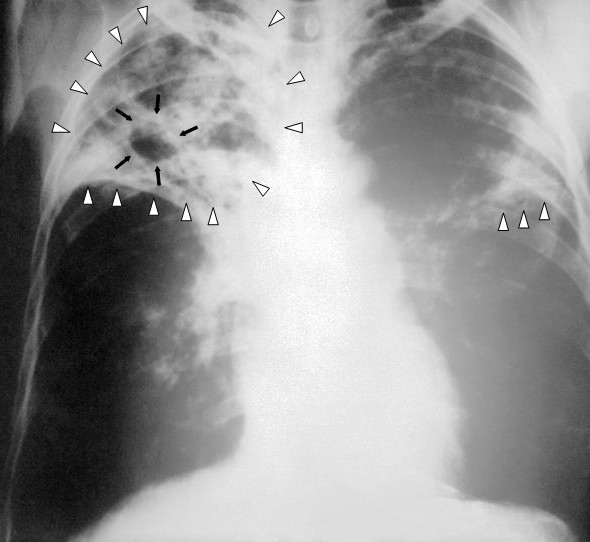

- Chest X-ray

Three common patterns of pneumonia may be detected on chest X-ray which include:

- Lobar pneumonia

- Bronchopneumonia

- Interstitial pneumonia

Tuberculosis (TB)

As a result of first-time exposure to aerosolized Mycobacterium tuberculosis, primary tuberculosis (TB) develops.

Tuberculosis (TB) results in the hilar lymph nodes undergoing fibrosis and calcification to produce a Ghon complex as well as localized, caseating necrosis of the lung.

Although primary tuberculosis (TB) usually has no symptoms, it results in a positive purified protein derivative (PPD) test result.

When Mycobacterium tuberculosis reactivates, secondary tuberculosis (TB) develops.

Reactivation of Mycobacterium tuberculosis is frequently caused by AIDS, although it can also be caused other immune compromising issues such as disease or advanced age.

Tuberculosis (TB) usually occurs at the lung’s apex due to the high oxygen tension in that region of the lungs.

Tuberculosis (TB) creates a cavitary foci of caseous necrosis and has the potential to cause tuberculous bronchopneumonia or miliary pulmonary tuberculosis.